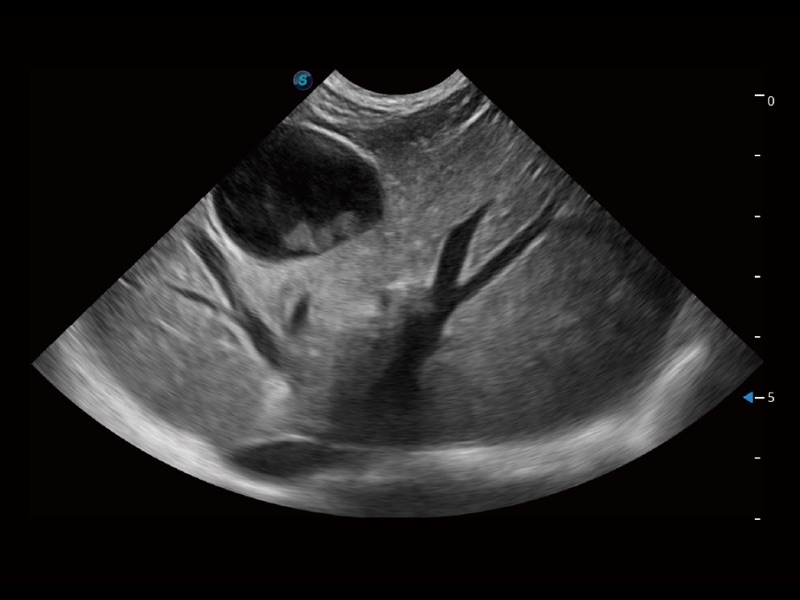

能够基于左心室壁追踪和辛普森法,自动计算射血分数,支持多个可移动点描迹,与手动测量相比,极大节省了动物医生的时间和精力。

通过360度任意调节3条M型取样线,在同一心动周期上观察心脏不同位置的运动曲线,得到准确的心功能测量数据,有效评估心肌运动及左心室功能。

实时用颜色表示心肌组织运动,观察和定量组织的运动情况,对快速检测与评估心肌的灌注和活性、电传导及心肌收缩和舒张功能等均能提供重要的诊断信息。